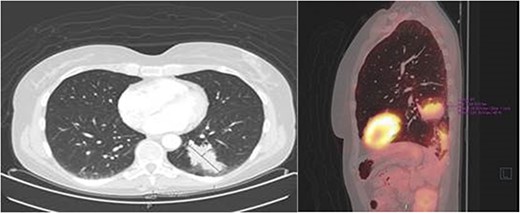

After 1 month of initial diagnosis, an excision of the tumour was performed through open approach with primary closure of the vaginal wall. Histopathological examination confirmed the solid tumour to be metastatic disease from rectal origin with free margins. The newly discovered symptoms related to the rectovaginal septum metastasis had completely disappeared following the excision. Upon further follow-up at 2 years and 6 months; routine lab results showed a significant increase in the CEA levels at 5.2 ug/l (3 months prior at 4.0 ug/l). Given this significant increase; a PET-scan was again performed. The PET-scan revealed a lesion within the left lower lobe of 5.7 cm in a transverse plane; suspected to be distant metastasis (see Fig. 3). Compared to the last PET-scan, this lesion was a new development not previously seen. CT-guided thoracic biopsy confirmed by histopathological examination, that this lesion was indeed a distant metastasis of the previous rectal cancer.

Transverse- and sagittal plane of the PET-scan showing a leasion in the left lower lobe with metabolic activity.